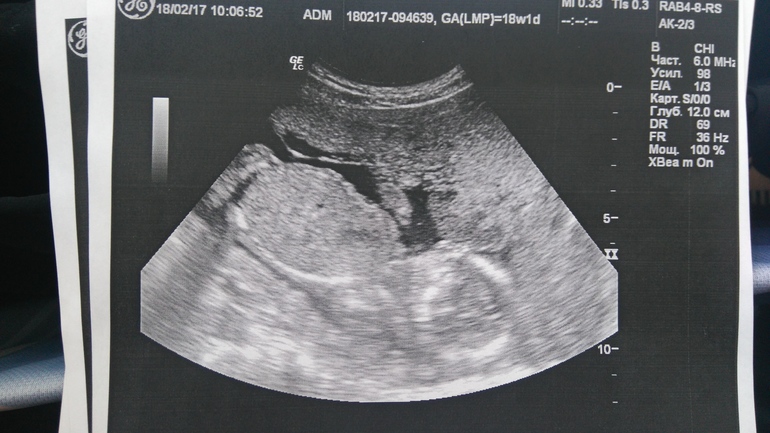

А так все хорошо, дитя и все его параметры соответствуют норме, весим 229г +-34г. Ну и главная интрига раскрылась - это мальчик!) Ура!))) А то свекр уже надоел, на день рождения мужа желал себе внука, а я, уже пузатая, добавила, что желательно с первого раза) Так и получается)) И вот панорамное фото, вид с горшка)

Попка, ляшки и 'погремушка')